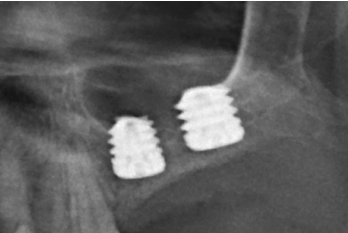

Se realiza la extracción de ambos y la regeneración de los alveolos con PRGF-Endoret para lograr el sellado de la perforación y una evolución lo más favorable posible para la posterior inserción de los implantes en la zona. Tras dos meses podemos observar en el Cone-Beam dental que la perforación se ha cerrado completamente pero el volumen óseo residual en altura para la inserción de los implantes es insuficiente, existiendo únicamente un 2 mm de altura ósea (Figuras 3 y 4).

Por ello, se decide llevar a cabo una elevación de seno utilizando biomaterial (hidroxiapatita bovina) unido a PRGF-Endoret. Se realiza la elevación y tras cinco meses se procede a la evaluación de un nuevo Cone-beam dental para poder visualizar la cantidad y calidad del injerto obtenido para la inserción de los implantes dentales. En los cortes correspondientes a los molares del primer cuadrante podemos observar una perfecta consolidación del injerto con la posibilidad de insertar implantes de 13 mm.